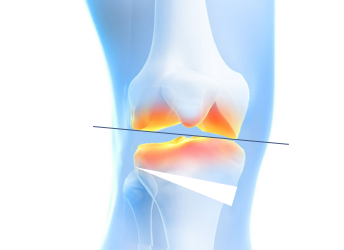

High Tibial Osteotomy (HTO)무릎 아래 뼈인 경골(정강이뼈)의 윗부분(근위부)을 절골하여 다리 정렬을 바로잡는 무릎 교정 수술입니다.

무릎 안쪽 관절이 닳아 O자 다리 형태로 휘어 통증이 생기는 경우, 다리의 축을 바로잡아 무릎 안쪽의 하중을 줄여주는 교정 수술입니다.

관절면과 평행하게 절골하여 각도를 교정